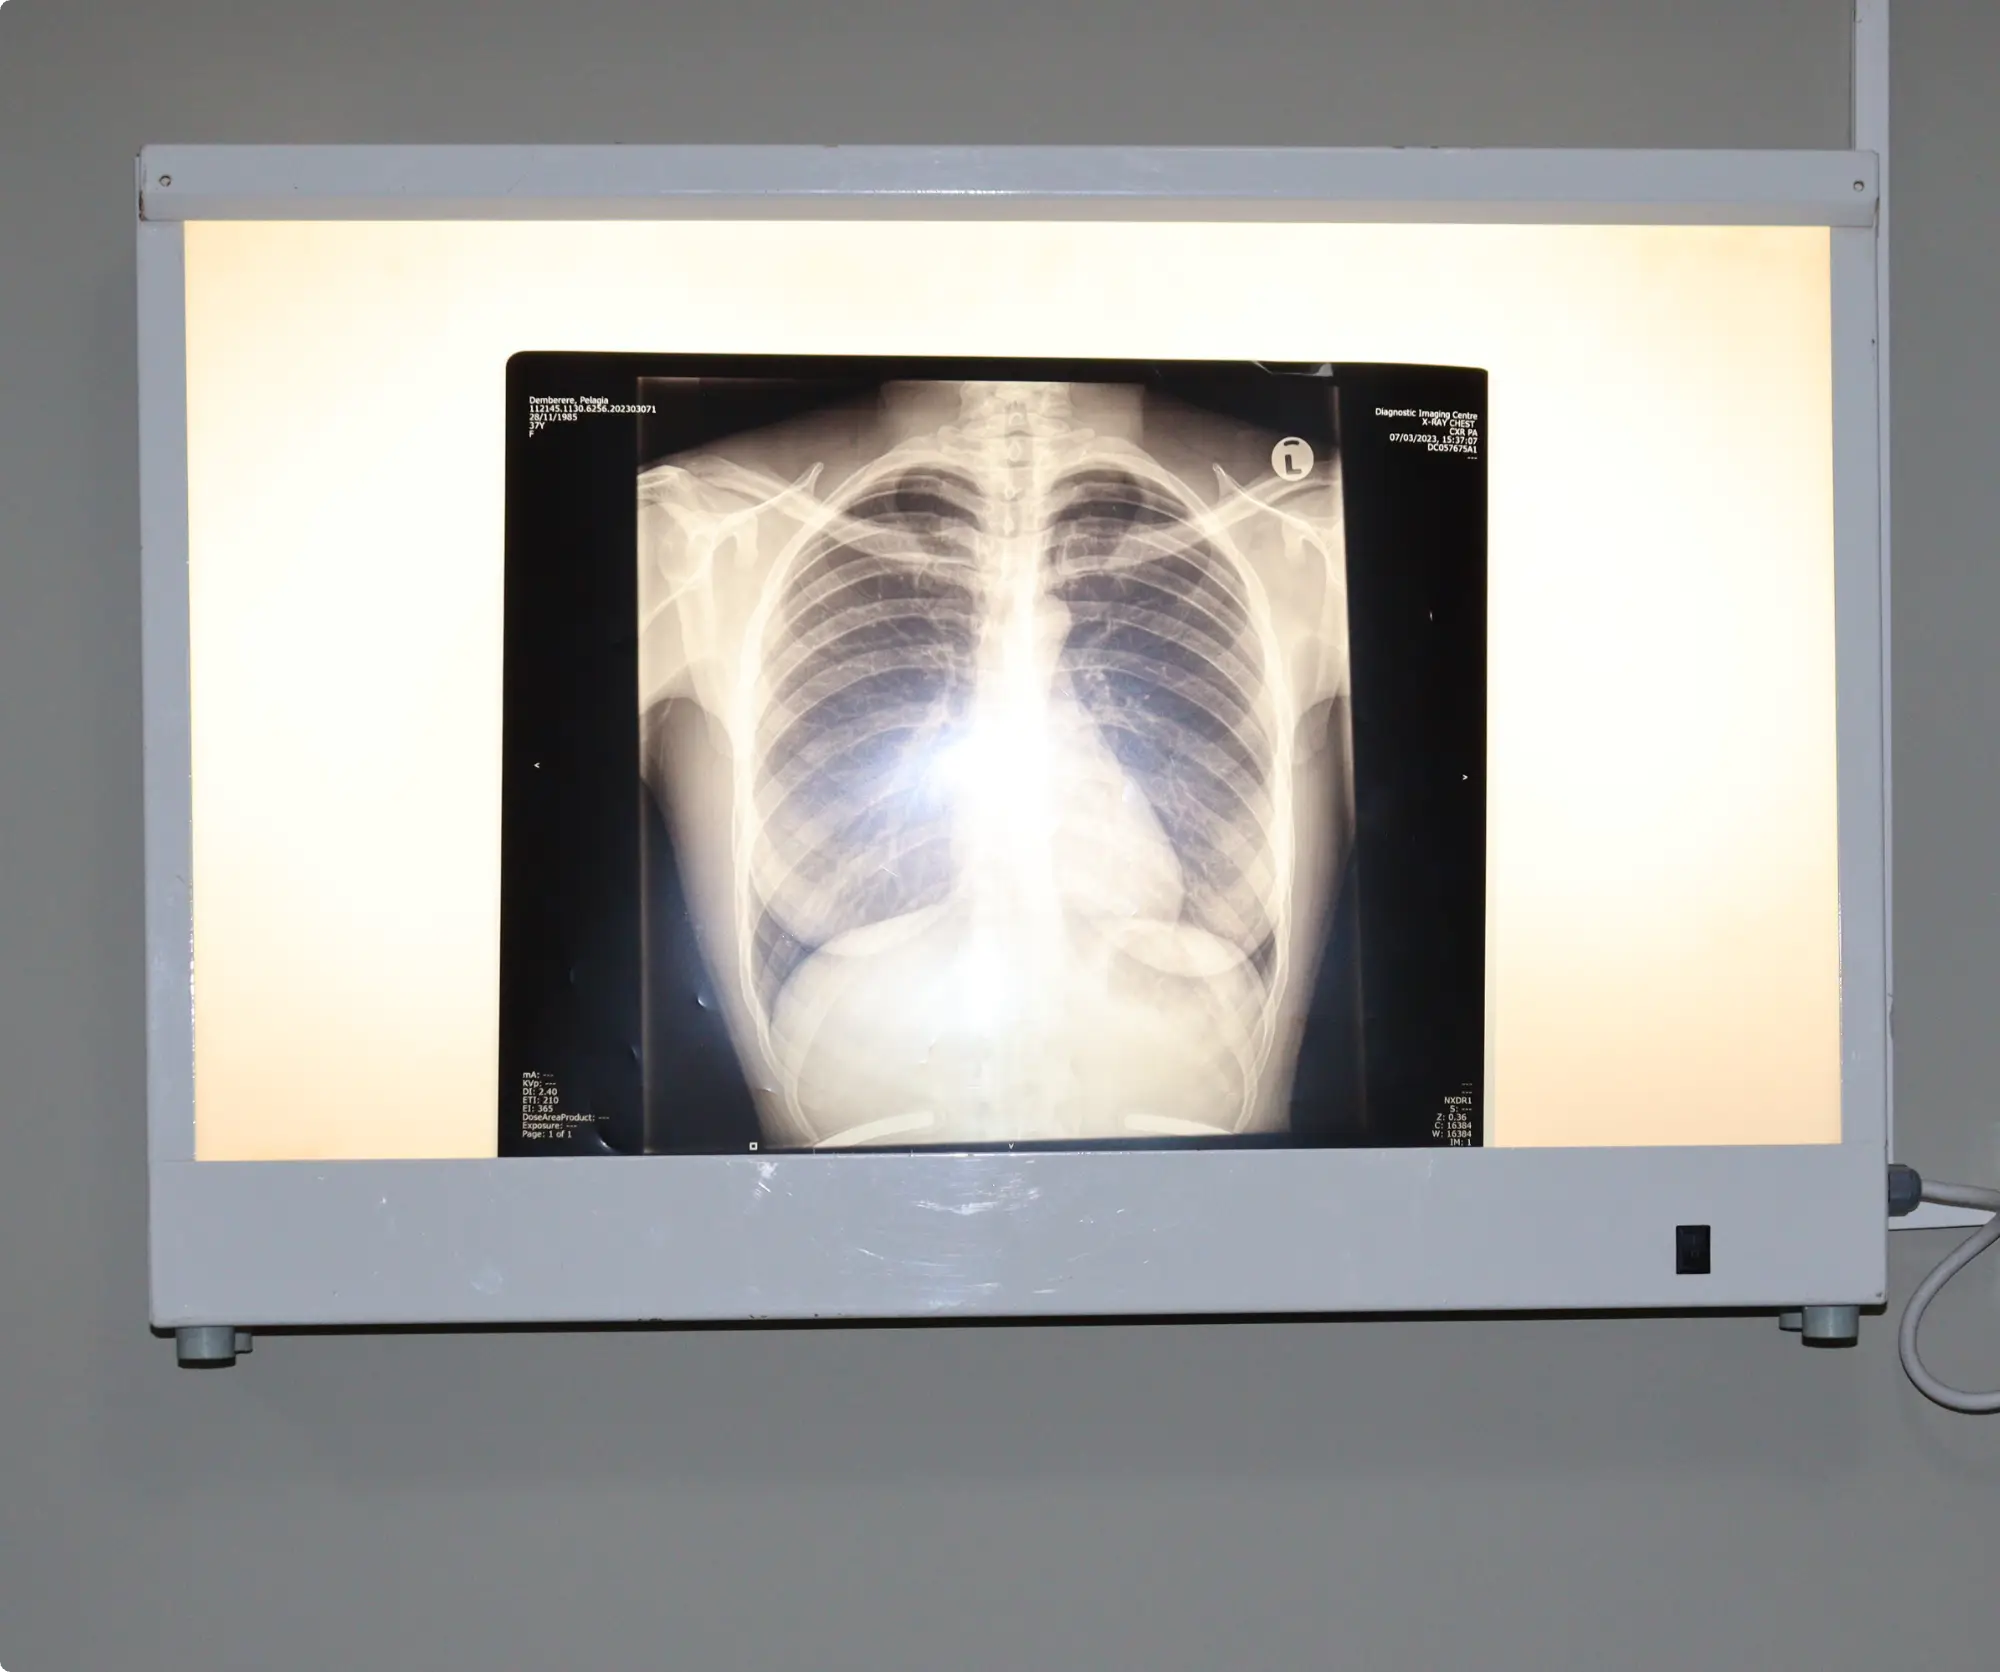

At Corporate 24's X-ray and Scan Centre, we provide essential radiology services focused on general X-rays and ultrasound scans. These vital diagnostic tools help accurately assess and monitor a wide range of health conditions, supporting effective treatment decisions.

• General X-rays: Fast and reliable imaging for evaluating bone fractures, chest conditions, and other common medical concerns. Our digital X-ray technology ensures clear images with minimal radiation exposure.